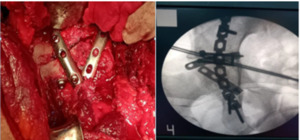

The induction of anesthesia was accompanied by the administration of prophylactic antibiotics (2 g of third-generation cephalosporin) to all patients who underwent spinal or epidural anesthesia. All patients underwent the same surgical procedure. They were set up in a lateral position. With the afflicted hip on the upper side and the thigh and leg free draped to be easy to move and manipulate during surgery to aid reduction, all fractures were revealed and stabilized using the K-L technique, which is the accepted gold standard in the treatment of posterior wall fractures. The gluteus maximus muscle was divided along the vascular plane after an incision was made in the skin, subcutaneous tissue, and fascia lata. After identification of the short external rotators, they were tagged, their ends were cut, and the sciatic nerve was protected. The fracture fragments were examined, any soft tissue pieces between the fragments were removed, and any associated capsular soft tissues were preserved [Figure 1A]. The osteochondral free fragments of the hip joint were removed, and the degree of marginal impaction was determined via the application of light traction. After that, portions of the posterior wall and their connected capsular ligaments were reduced and kept in place using a sharp ball spike. Kirshner wires were occasionally used after the final reduction was complete [Figure 1B]. A 3 or 4hole one-third tubular plate was modified by cutting a small central portion of the terminal hole of the plate. This process leaves 2 adjacent end prongs. Both prongs are bent at an angle of 60 to 90 degrees toward the undersurface of the plate. The hooks were designed to press on the bone fragments but not into the labrum. A 2-mm Kirschner wire (K-wire) was used to hold the comminuted wall fragments in a reduced position. The K-wire was positioned behind the bony rim of the acetabular wall fragment, which was directed away from the intra-articular marginal rim surface to avoid penetration of the joint space. The spring plates were placed at 90 degrees to the articular fragments creating a buttress effect. The medial hole of the spring plate was fixed to the retroacetabular bone with a 3.5-mm cortical screw. Compression of the malleable straight spring plate led to better contouring of the retroacetabular surface, increasing compression of the joint fragments. Spring plates were not precontoured to anatomically fit the residual intact bone. A pelvic reconstruction (straight or curved) compression plate, usually from 8 to 10 holes in length, is placed over the spring plates to increase the stability of the spring plate effect and prevent postoperative loss of fixation. The spring hook plates were extended medially beyond the longer buttress plate. All patients underwent open reduction and internal fixation with a precontoured one-third tubular plate (spring plate) [Figure 1C], which was secured with one or two 3.5 mm cortical screws and reinforced with a 3.5 mm reconstruction plate [Figure 1D]. Following fixation, a stability test and moderate traction at the hip joint were used to confirm intra-articular reduction. With the use of suction drainage tubes, the incisions were stitched and closed in layers.